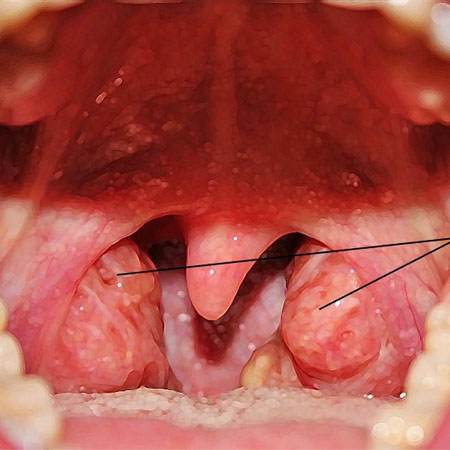

Аденоиды — это увеличение носоглоточной миндалины, которую еще называют нёбной. Этот недуг вызывает нарушения носового дыхания вплоть до полного отсутствия возможности дышать носом. Нередко аденоиды становятся причиной патологического снижения слуха у ребенка.

Воспаление вызывает разрастание лимфоидной ткани, миндалина утолщается. По тому, насколько она видоизменена, врачи определяют степень заболевания.

- Первая степень. Миндалина увеличена, разрастание незначительное, не превышает половины просвета. Носовое дыхание нарушено незначительно.

- Вторая степень. Носоглоточная миндалина разрослась настолько, что закрывает две три просвета. Носовое дыхание существенно нарушено.

- Третья степень. Глоточная миндалина воспалена и увеличена, носовое дыхание отсутствует, так как она закрывает просвет почти целиком.